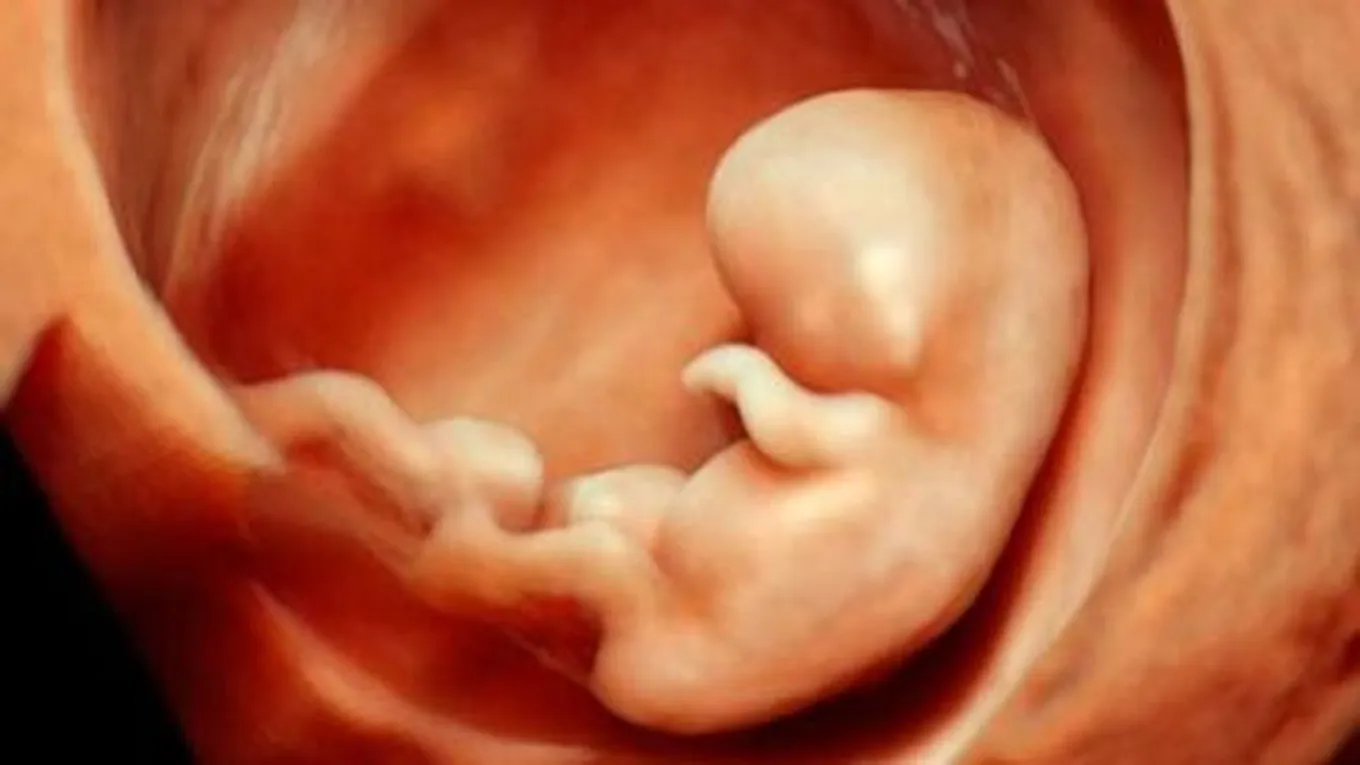

الجنين في الأسبوع العاشر

تطور الجنين في الأسبوع العاشر

في هذه المرحلة يبلغ طول الجنين 2-3 سنتيمتر، ويصل وزنه إلى 2.5 غرام. تبدأ التفاصيل الدقيقة بالبروز، فتنمو الأذنان ويصبح الطفل قادراً على سماع الأصوات الخارجية وتمييزها والتفاعل معها، لكنّها تنمو في مكان منخفض من الرأس، وفي مراحل متقدّمة ومع استمرار نمو الجنين تتحرّكان لتستقرّا على جانب الرأس.

تبدأ العيون أيضاً بالنمو ولكنها تكون مغطّاةً بالجفون لحمايتها، وتبقى كذلك حتى الأسبوع السابع والعشرين، وتنمو في هذه المرحلة أيضاً براعم الأسنان والتي يبلغ عددها 20 برعماً، وتُشكّل الأسنان اللبنية التي تظهر في الأعوام الأولى من حياته، ومن التفاصيل التي تبدأ بالظهور بشكل أوضح في هذه المرحلة الأصابع؛ حيثُ تبدأ بالانفصال عن بعضها البعض وتصبح أطول وأقوى .